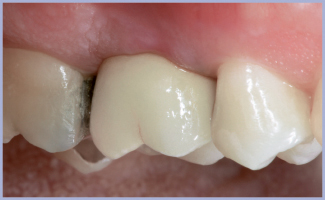

- Fig. 2 – Aspetto dei tessuti molli a 5 mesi

- Fig. 3 – Guarigione dei tessuti

Si rimuove il cemento in eccesso (fig. 27) e si posiziona in maniera definitiva in bocca il restauro protesico che provoca una leggera ischemia a carico dei tessuti molli attorno alla corona (fig. 28) dovuta al condizionamento realizzato in sede di progettazione e realizzazione del lavoro (fig. 8). Il controllo clinico e radiografico ad 1 anno di distanza dall’intervento implantare (figg. 29, 30) mostra come il condizionamento gengivale effettuato dalla protesi abbia influito positivamente sull’estetica coprendo tutti gli spazi interdentali. Questo effetto è rimasto inalterato nel tempo grazie al supporto offerto dall’osso peri-implantare che si è perfettamente mantenuto.

- Fig. 30 – Aspetto dei tessuti ad 1 anno